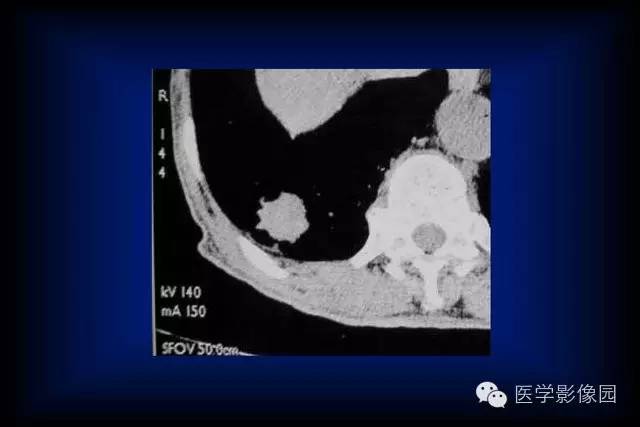

肺癌的CT征象及其病理基础